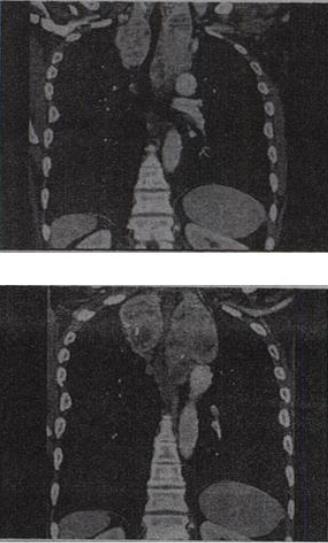

男,33岁,颈部包块半年余,可随吞咽上下移动,结合影像学检查,最可能的诊断是()。

A、胸腺瘤

B、淋巴瘤

C、纵隔畸胎瘤

D、淋巴管瘤

E、胸骨后甲状腺肿

正确答案:

E